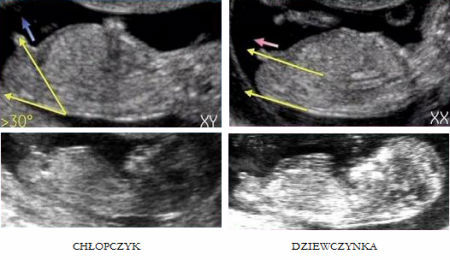

W poprzedniej ciązy mi gin powiedziała w 14 tygodniu ze będzie chłopiec ale pewna nie jest... i tłumaczyła ze i dziewczynki i chłopcy mają takie "fałdy skórne" a płeć ocenia się na podstawie ich "oddalenia" od siebie ( a dokładnie jak ten fiutek pada względem pleców - równolegle czy pod kątem) a nie tego czy dziecko ma coś miedzy nogami... BO KAŻDE MA! W pierwszej ciąży te ocenianie się sprawdziło ale i tak miałam świadomość "że coś może się zmienić" -mimo że czułam sama chłopaka. Teraz niby cieszę się że będzie mały Adrianek ale jednak czekam z utęsknieniem na te USG 3d połówkowe bo wtedy potwierdzi się płeć. Bo faktycznie już będzie widać "jajeczka" albo i nie...

Tu widać o co chodzi z tym ocenianiem:

To są zdjęcia z około 14 tygodnia właśnie... dlatego mówię ze to jest takie bardzo subtelne... U mnie i u Blue już jest bardziej prawdopodobny chłopak bo płeć oceniana była później (około 16) Ale te wróżenie na genetycznym moze się sprawdzić ale wcale nie musi...